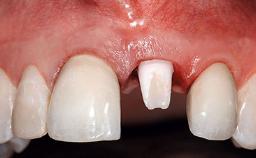

A 32-year-old female Caucasian patient with a compromised maxillary right central incisor was referred to us by a general dentist. Her chief complaints were discomfort and mobility of tooth 11 with unsatisfactory esthetics due to discoloration. The patient reported a previous trauma, some years earlier, as the origin of pathology on the afflicted tooth. Anamnesis was negative for any other dental or periodontal pathology in the remaining dentition. The patient did not take any medication and reported to be a light smoker (5–10 cigs/day). She had high esthetic expectations of her treatment. The extraoral examination revealed a high smile line with full exposure of her maxillary teeth and surrounding soft tissue in the area between the second premolars.

Lip Line No exposure of papillae Exposure of papillae Full exposure of mucosa margin

Periodontal Phenotype Low-scalloped, thick Medium-scalloped, medium-thick High-scalloped, thin

Shape of Tooth Crowns Rectangular Triangular